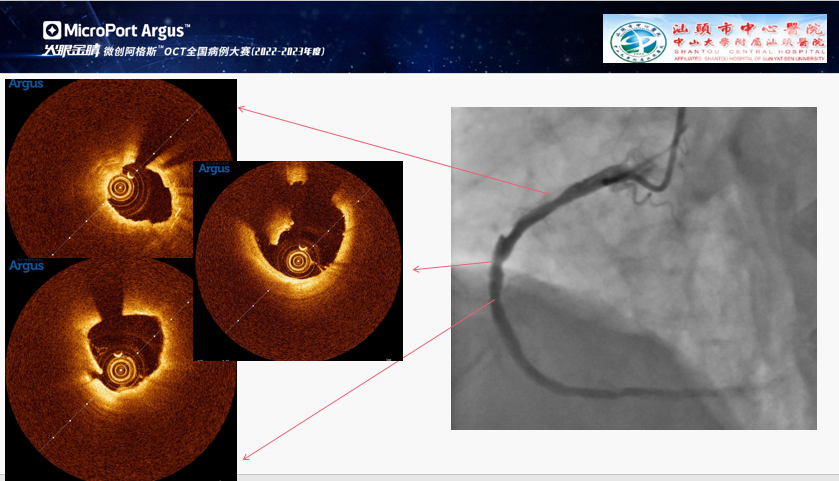

郑晓东:OCT指导亚急性支架内血栓治疗

患者为72岁男性,6天前因下壁STEMI行急诊PCI。术后2天患者胸痛再发,冠脉造影可见RCA近中段支架影,支架内可疑血栓形成。为了明确患者术后短时间内支架内血栓形成的原因从而予以针对性治疗,术者对病变处进行了OCT检查。根据OCT图像,可见原支架局部膨胀不全,支架内及支架以远血栓形成,可见溃疡性病变,考虑血栓形成可能与原支架边缘夹层、溃疡病变未完全覆盖、支架膨胀不全相关。

因此,术者使用4.0**10mm球囊扩张RCA原支架,并在原支架以远串联植入一枚3.5*10mm的药物支架,复查OCT可见RCA原支架膨胀情况改善,支架内最小管腔面积MSA 6.12mm²,管腔内血栓负荷明显降低,支架边缘无夹层及血肿,复查造影结果满意。

该病例为亚急性支架内血栓形成,使用OCT探寻支架血栓形成的原因,对于选择进一步治疗策略具有重要意义。手术过程中使用微创阿格斯™OCT发现原支架膨胀不全,远端存在夹层。由此可见,OCT可以精确评估支架膨胀或者贴壁的情况,对支架边缘的夹层以及血栓也有很高的敏感性。